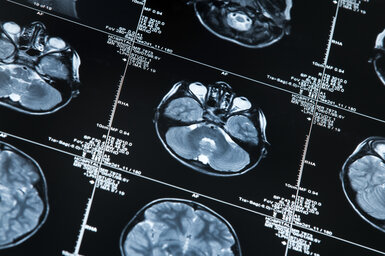

MRI scan of a human head

EMPIR project developing non-invasive techniques for diseases such as Alzheimer’s and Parkinson’s has a number of successful outcomes

Recently completed EMPIR project Innovative measurements for improved diagnosis and management of neurodegenerative diseases (15HLT04, NeuroMET) developed reference measurement procedures to accelerate the uptake of minimal invasive methods for the early diagnosis and monitoring of the progression of neurodegenerative diseases such as Alzheimer’s and Parkinson’s. The research explored innovative techniques for early diagnosis and monitoring, based on non-invasive blood and saliva tests, in-vivo magnetic resonance approaches and cognitive assessments.